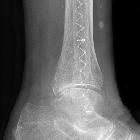

Osteosynthese am Außenknöchel mit Illuminoss. Polymerimplantat für minimalinvasive Frakturstabilisierung. Vorteil: Minimalinvasiv einzubringen z.B. bei Weichteilinfekt. Monomer wird lichtinduziert polymerisiert.